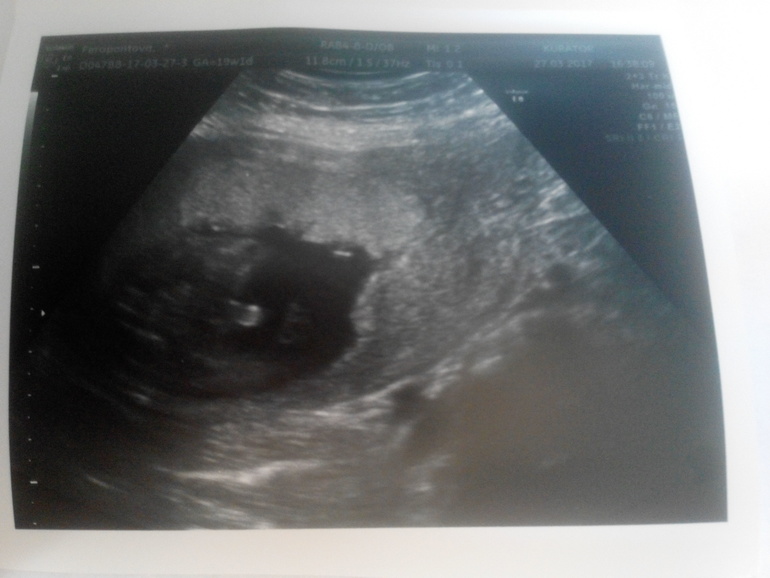

19 недель ровно а по УЗИ 18.3